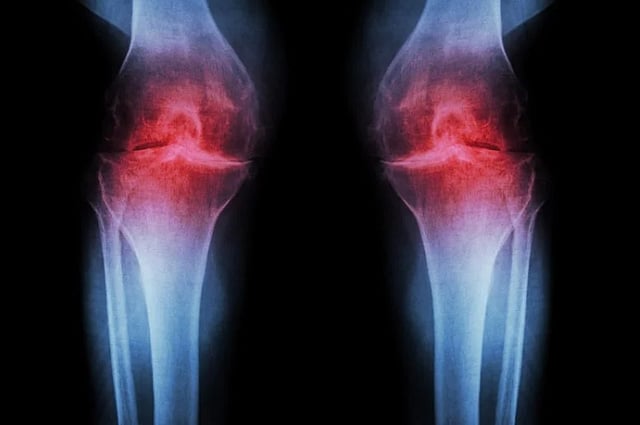

CARTILAGE is a soft tissue that cushions joints. Once it tears or breaks down, it rarely repairs itself, often leading to joint pain and stiffness. Stock photo.

For millions of people, arthritis is a painful reminder of aging or past injury. Osteoarthritis, the most common form, develops when cartilage in the joints wears down over time. This cushioning tissue allows bones to move smoothly, but once it breaks down, it rarely repairs itself.